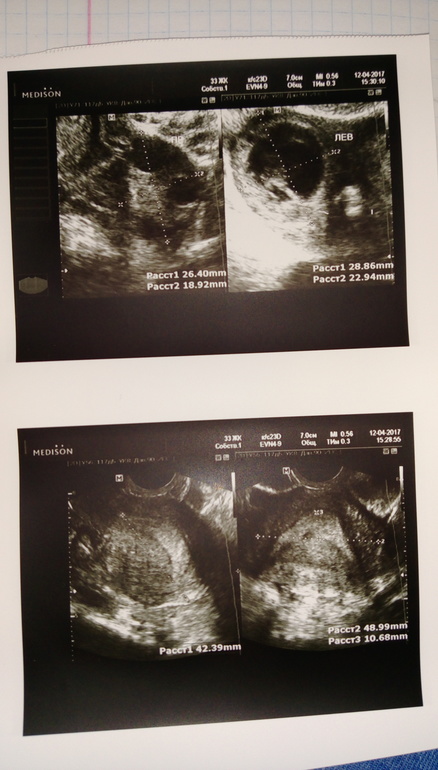

Сегодня было на узи

Врач сказал все хорошо эндрометрия и было овуляция на 14 дц

Сейчас 19 дц 4 дпо